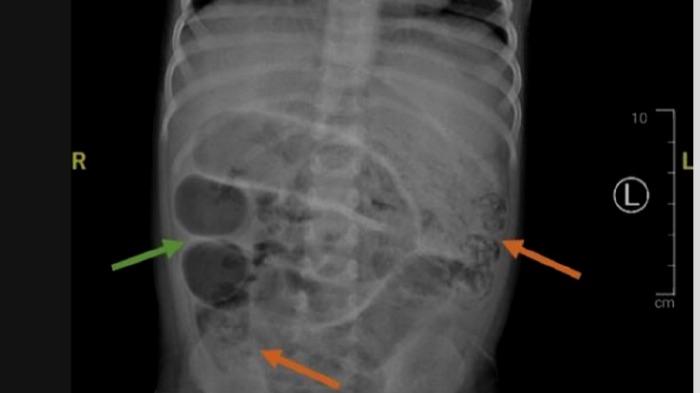

Perut anak usia 3 tahun yang berasal dari Kabupaten Jember, Jawa Timur itu dirontgen dan akhirnya terungkap penyebabnya.

Anak usia 3 tahun itu mengalami sumbatan di ususnya.

Tak disangka gumpalan di ususnya itu dipenuhi dengan cacing sehingga tidak bisa buang air besar (BAB).

Cacing tersebut menumpuk di dalam usus anak tersebut sehingga menyebabkan ususnya tidak berfungsi maksimal.